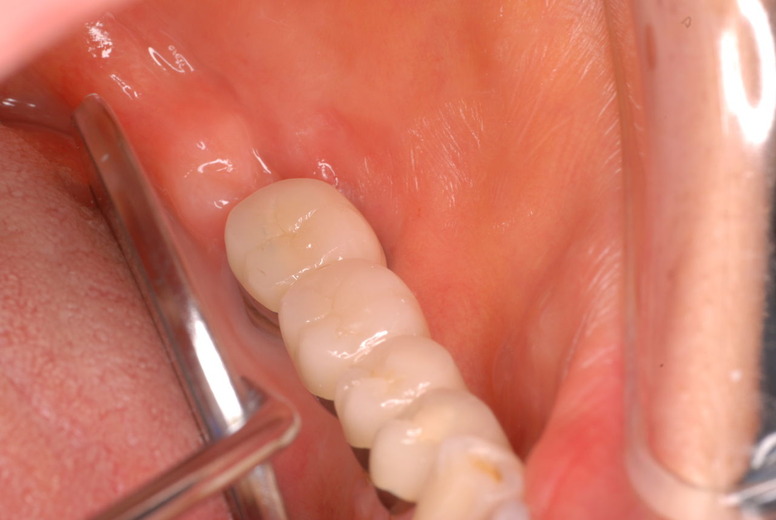

写真左下の親知らずが痛くなり抜歯しました。その後歯茎を除去して虫歯を露出させる処置を二回ほどしています。

レントゲンでは小さいですが、こう言う虫歯が一番怖いのです。

治療の成功率は極めて悪くすぐ再発しやすいのです。